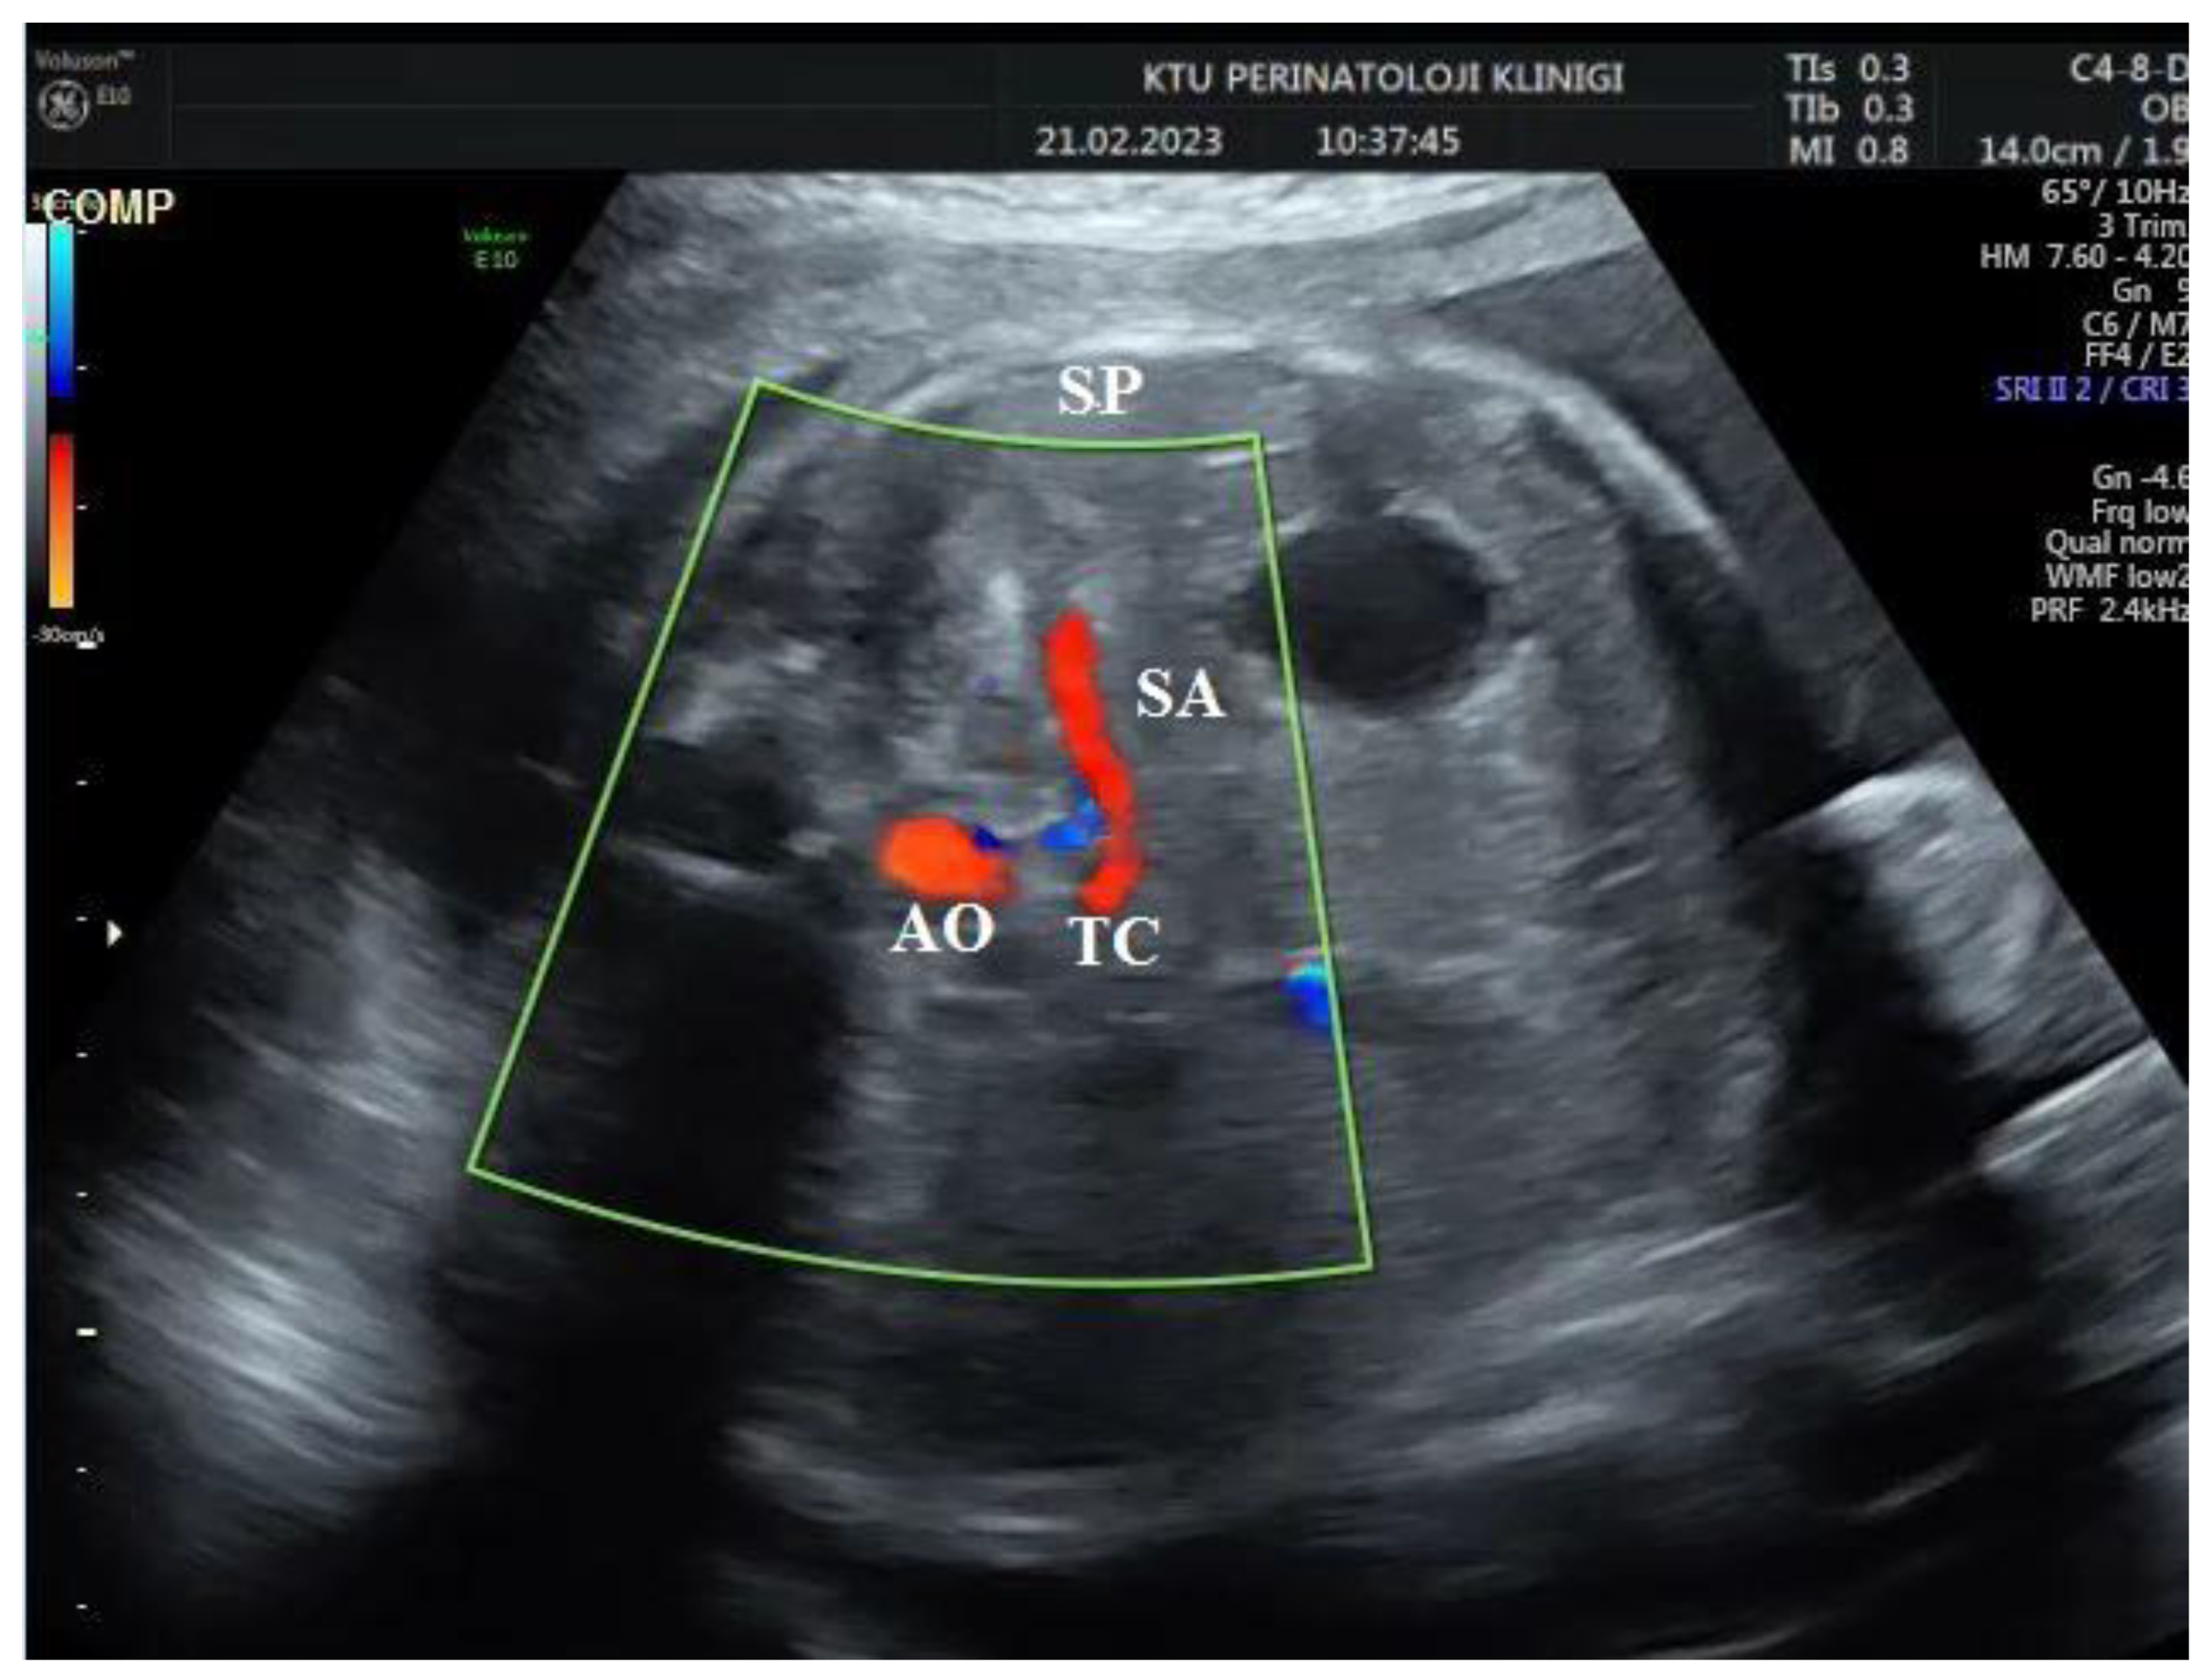

During the Doppler assessment, the patient was positioned on the examination table in a supine posture. It was measured when the fetus was inactive. A standard AC axial section view was obtained. Stomac pocket was visualized. Color Doppler was placed on the upper part of the stomach pocket and the splenic artery was visualized at the entrance to the spleen. Later, it was observed that the trace progressed towards the truncus celiacus and abdominal aorta. Color Doppler was placed at the entrance to the spleen with a 0-degree insomination angle, without the splenic artery entering the spleen. Fetal splenic artery Doppler parameters Peak systolic velocity (PSV), Pulsatility index (PI), Resistivity index (RI) and End diastolic velocity (EDV) were measured in all cases (Figure 1 and Figure 2).

Figure 2. Two-dimensional ultrasonographic imaging in the axial plane of the 30-week-old fetus shows the origin of fetal splenic artery from truncus cealiacus (TC; truncus cealiacus, AO; Aorta, SA; Splenic artery, SP; Fetal Spleen).